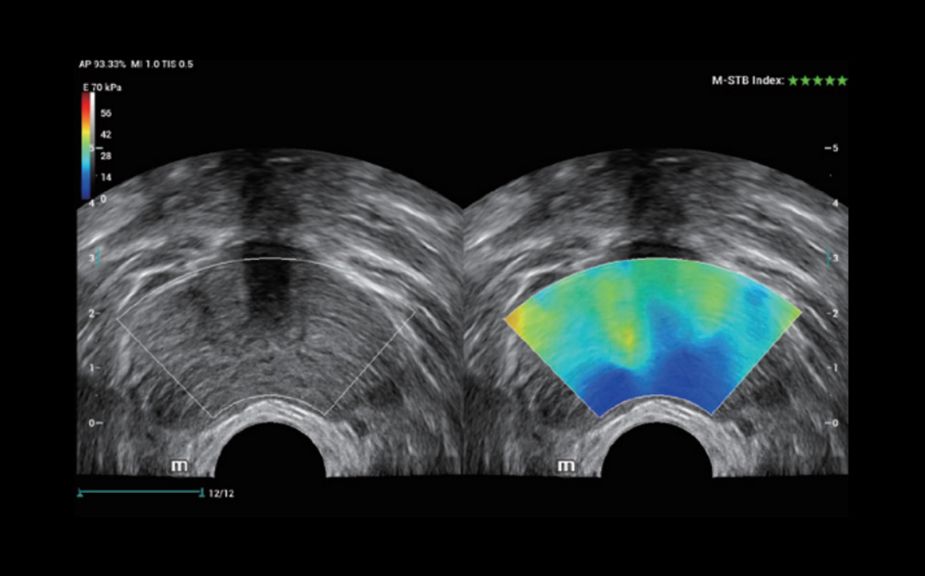

Innovative Stiffness Assessment: HiFR STE

Up to 10 times faster frame rate with smooth STE imaging display

More sensitive motion detection for better stability and greater accuracy

HiFR STE of breast cancer

HiFR STE of liver

Innovative Stiffness Assessment: HiFR STE

Up to 10 times faster frame rate with smooth STE imaging display

More sensitive motion detection for better stability and greater accuracy

HiFR STE of breast cancer

HiFR STE of liver